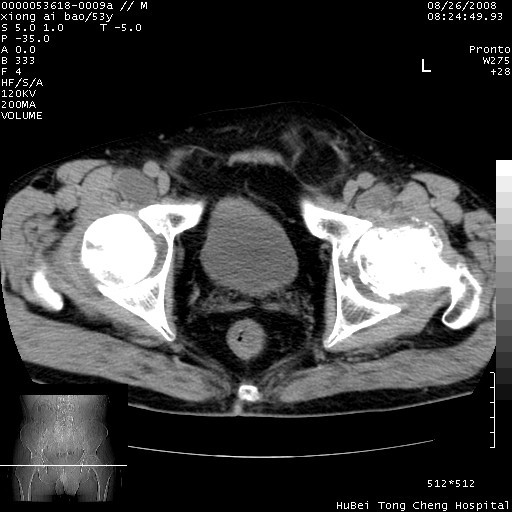

标题: CT15583:M,53Y。请老师指教分析骨盆及其他病变。 [打印本页]

标题: CT15583:M,53Y。请老师指教分析骨盆及其他病变。

双侧股骨头无菌坏死,左侧腹股沟斜疝。

非常典型病例,双侧股骨头坏死伴双髋关节周围软组织肿胀,左腹股沟疝。

双侧股骨头坏死伴双髋关节周围软组织肿胀,左腹股沟疝。

双侧骨股头无菌性坏死,左侧腹股沟疝

双侧髋关节肿胀明显,感觉还不能排除结核。

考虑双侧髋关节结核,左侧腹股沟疝